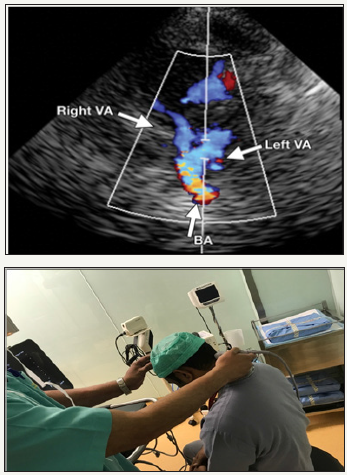

Transformational or sub occipital approach involve placing the transducer in sub occipital region in a flex neck, in mid line below the occipital, medial to the mastoid process and the probe is angled or tilted towards the bridge of the nose or contra lateral eye to insonate portion of the vertebral artery (VA) at a depth of 50-75mm (flow away from the probe) and further upward and medial tilting of probe is done to obtained from the basilar artery (BA) at a depth of 75-110mm (Figure 5).

Figure 6: Color Doppler flow image obtained with a Transformational or sub occipital window shows the vessels of the posterior cerebral circulation.